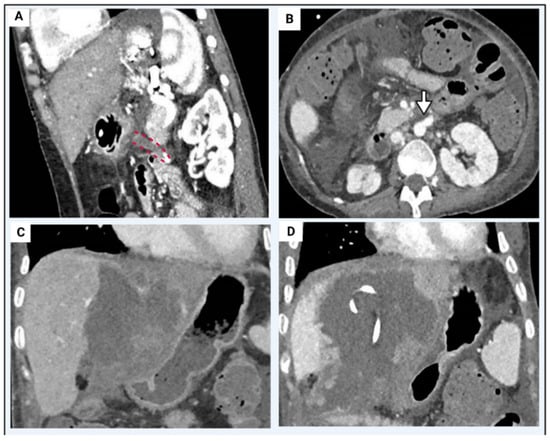

5.3. Portal Vein Thrombosis

| Grade | Extension |

|---|---|

| Grade I | <50% of the vessel lumen with or without minimal extension into the superior mesenteric vein (SMV). |

| Grade II | >50% occlusion of the PV, including total occlusions, with or without minimal extension into the SMV. |

| Grade III | Complete thrombosis of both PV and proximal SMV. Distal SMV is open. |

| Grade IV | Complete thrombosis of the PV and proximal, as well as distal, SMV. |